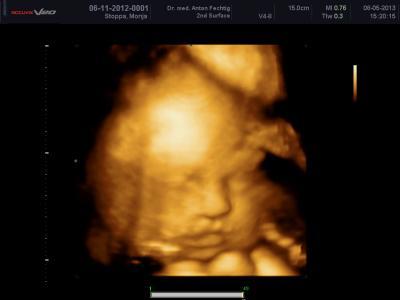

Meine kleine endwickelt sich süper. Sie wiegt jetzt ca 1820 gramm und ist ca 43 cm groß. Ich verliebe mich immer wieder in meine kleine Prinzessin wenn ich sie sehe < 3

Bild zu Fa Bericht von Mittwoch - Forum für Juli - Mamis